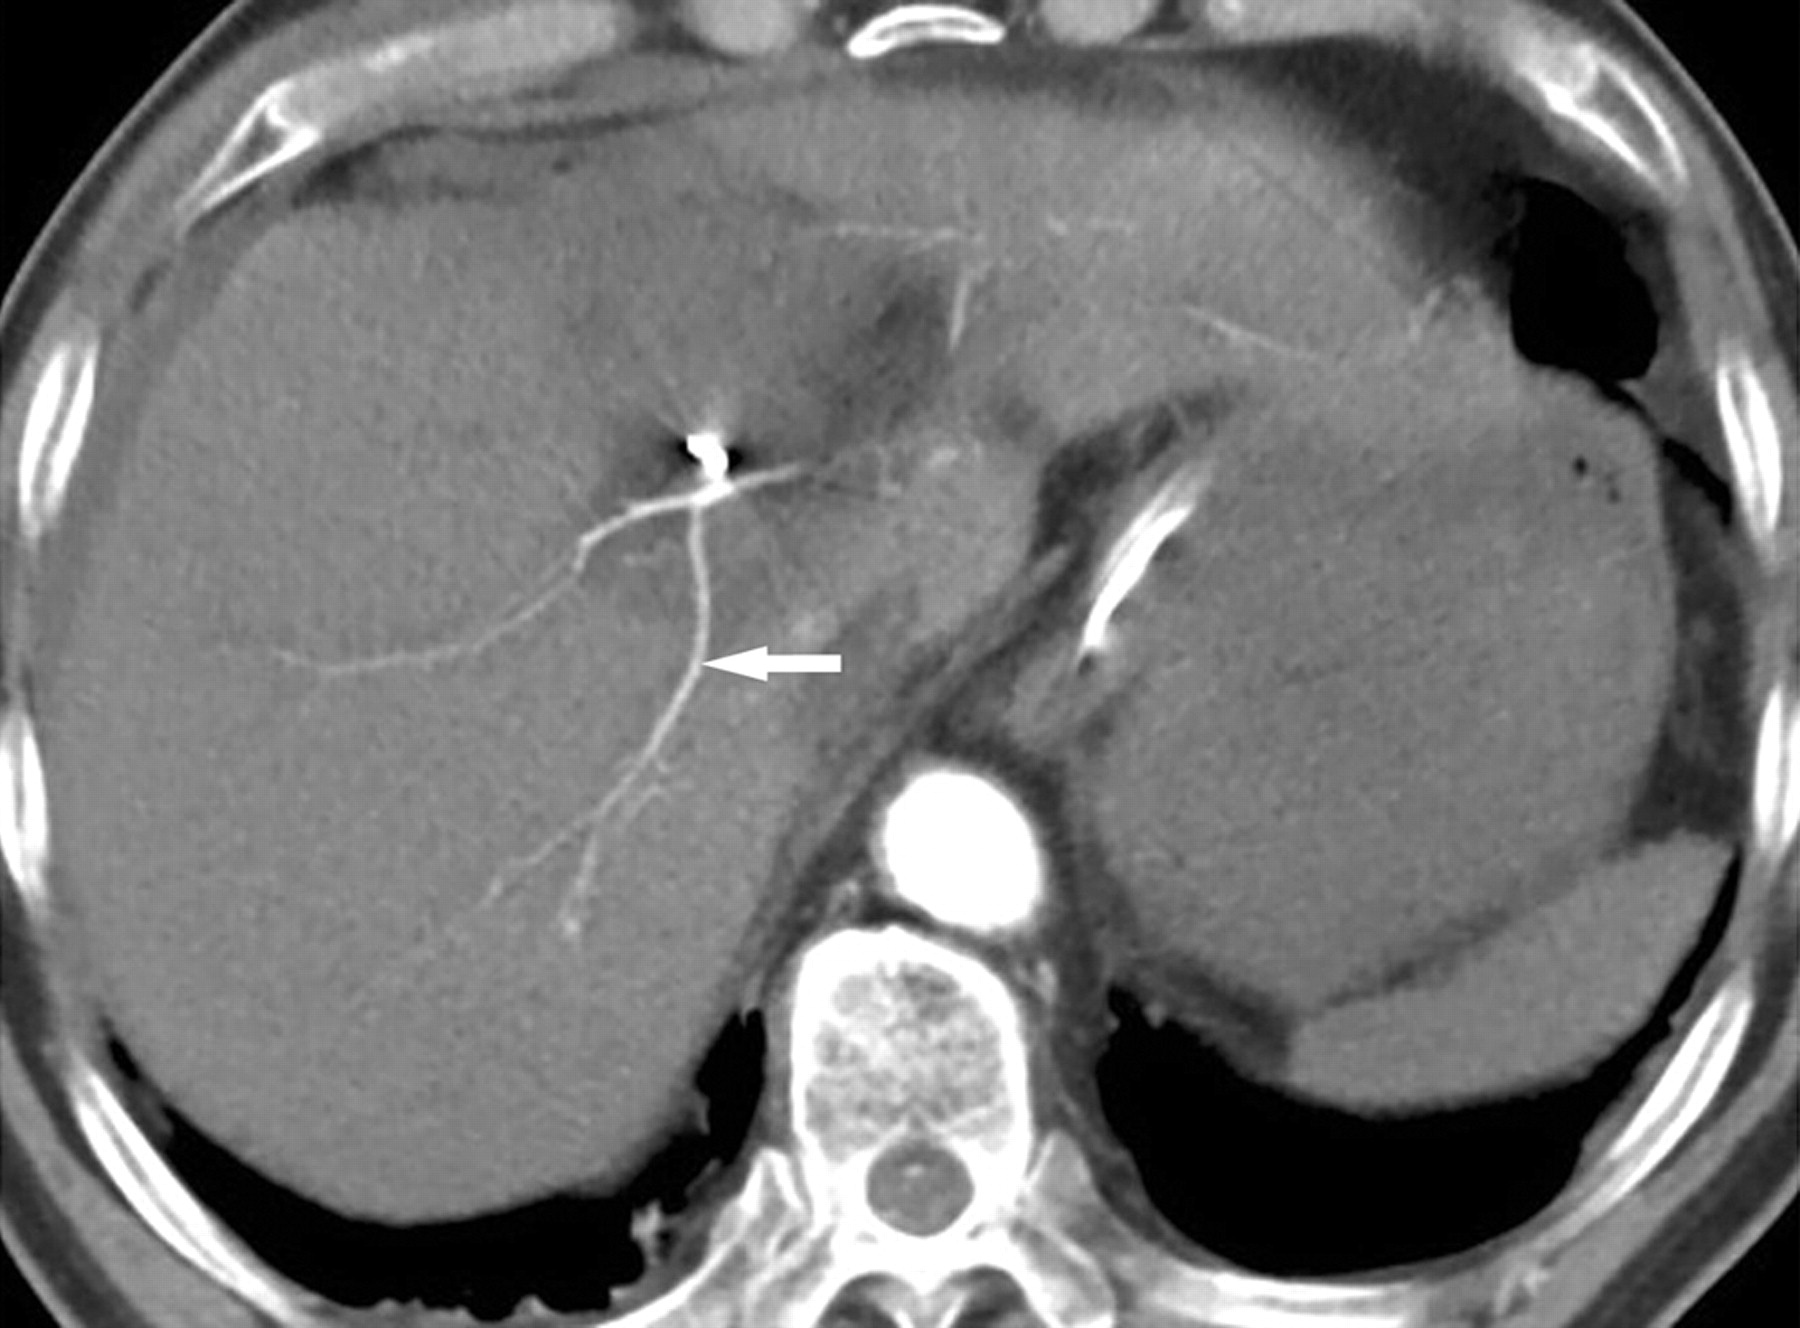

Сосудистые проявления гиповолемии.